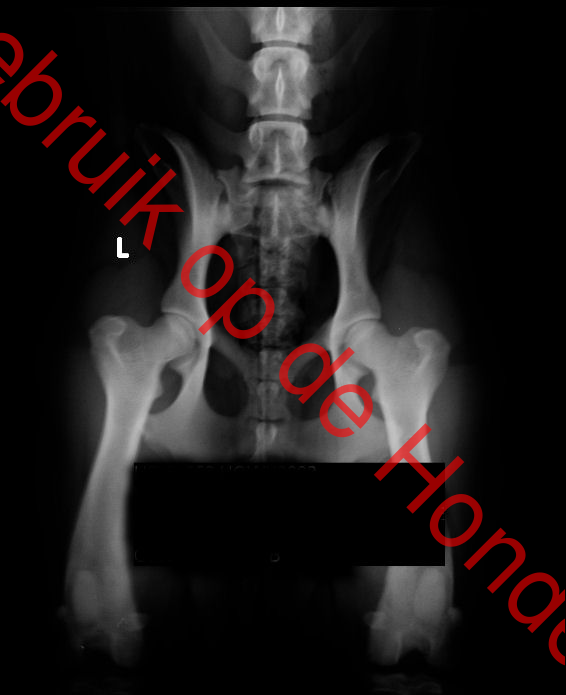

de ellebogen= vrij ,heupen= hd A, ogen=vrij,

fokker heup foto (jpg)